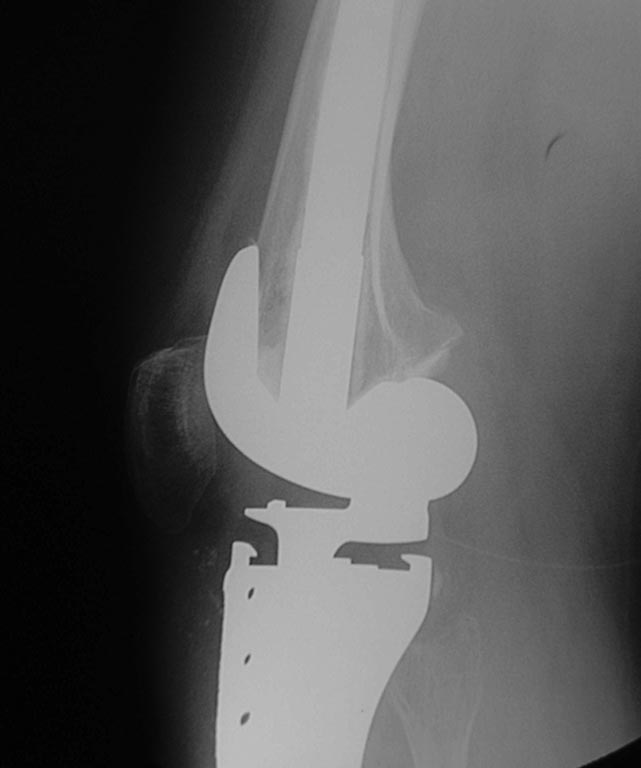

ка1кч432Уважаемые коллеги помогите с дальнейшей тактикой лечения.Больная

1976 г.р оперирована в октябре 2012 по поводу остеобластокластомы

проксимального метафиза пр.большеберцовой кости модульным имплантом

stryker послеоперационное течение гладкое.Ходит с полной

нагрузкой.Незначительно прихрамывая на пр.ногу .П/о рубец до 20 см без

признаков воспаления Пальпаторно по передней поверхности метаэпифиза

ю/берцовой кости .Активного разгибания нет ,и собственная связка

надколенника не контурирует.Пассивные движения в полном обьеме.На

контрольных рентгенограммах признаков нестабильности нет.В течении

последних трех недель появилось по передней поверхности пр.голени

серома.Пунктирована несколько раз– прозрачная синовиальная

жидкость.Взята на посев–чуствительна к гентомицину,цефазолину

,цефтриаксону и левофлоксацину.В настоящее время получает цефазолин 1.0

в/м 3 раза и гентомицин 160 мг в/м 1 раз.(уже 5 дней)Динамики нет,

жидкость продолжает скапливаться примерно в том же обьёме.